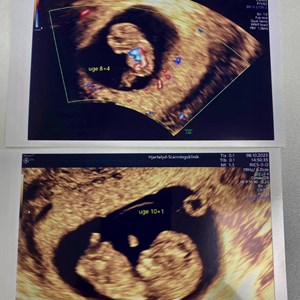

Bare 11 dage mellem de 2 billeder ! Fantastisk hvilket potentiale der er i sammensmeltnin...

19. september 2023